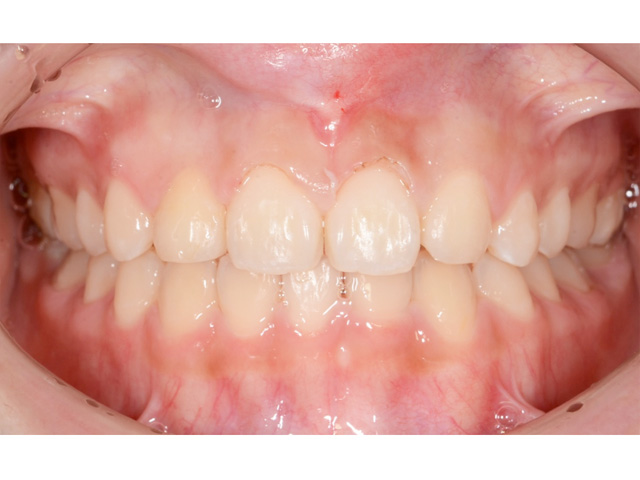

約2年半の矯正治療で、とてもキレイな歯ならびになり、自信にあふれる輝くような笑顔を得ることができました。